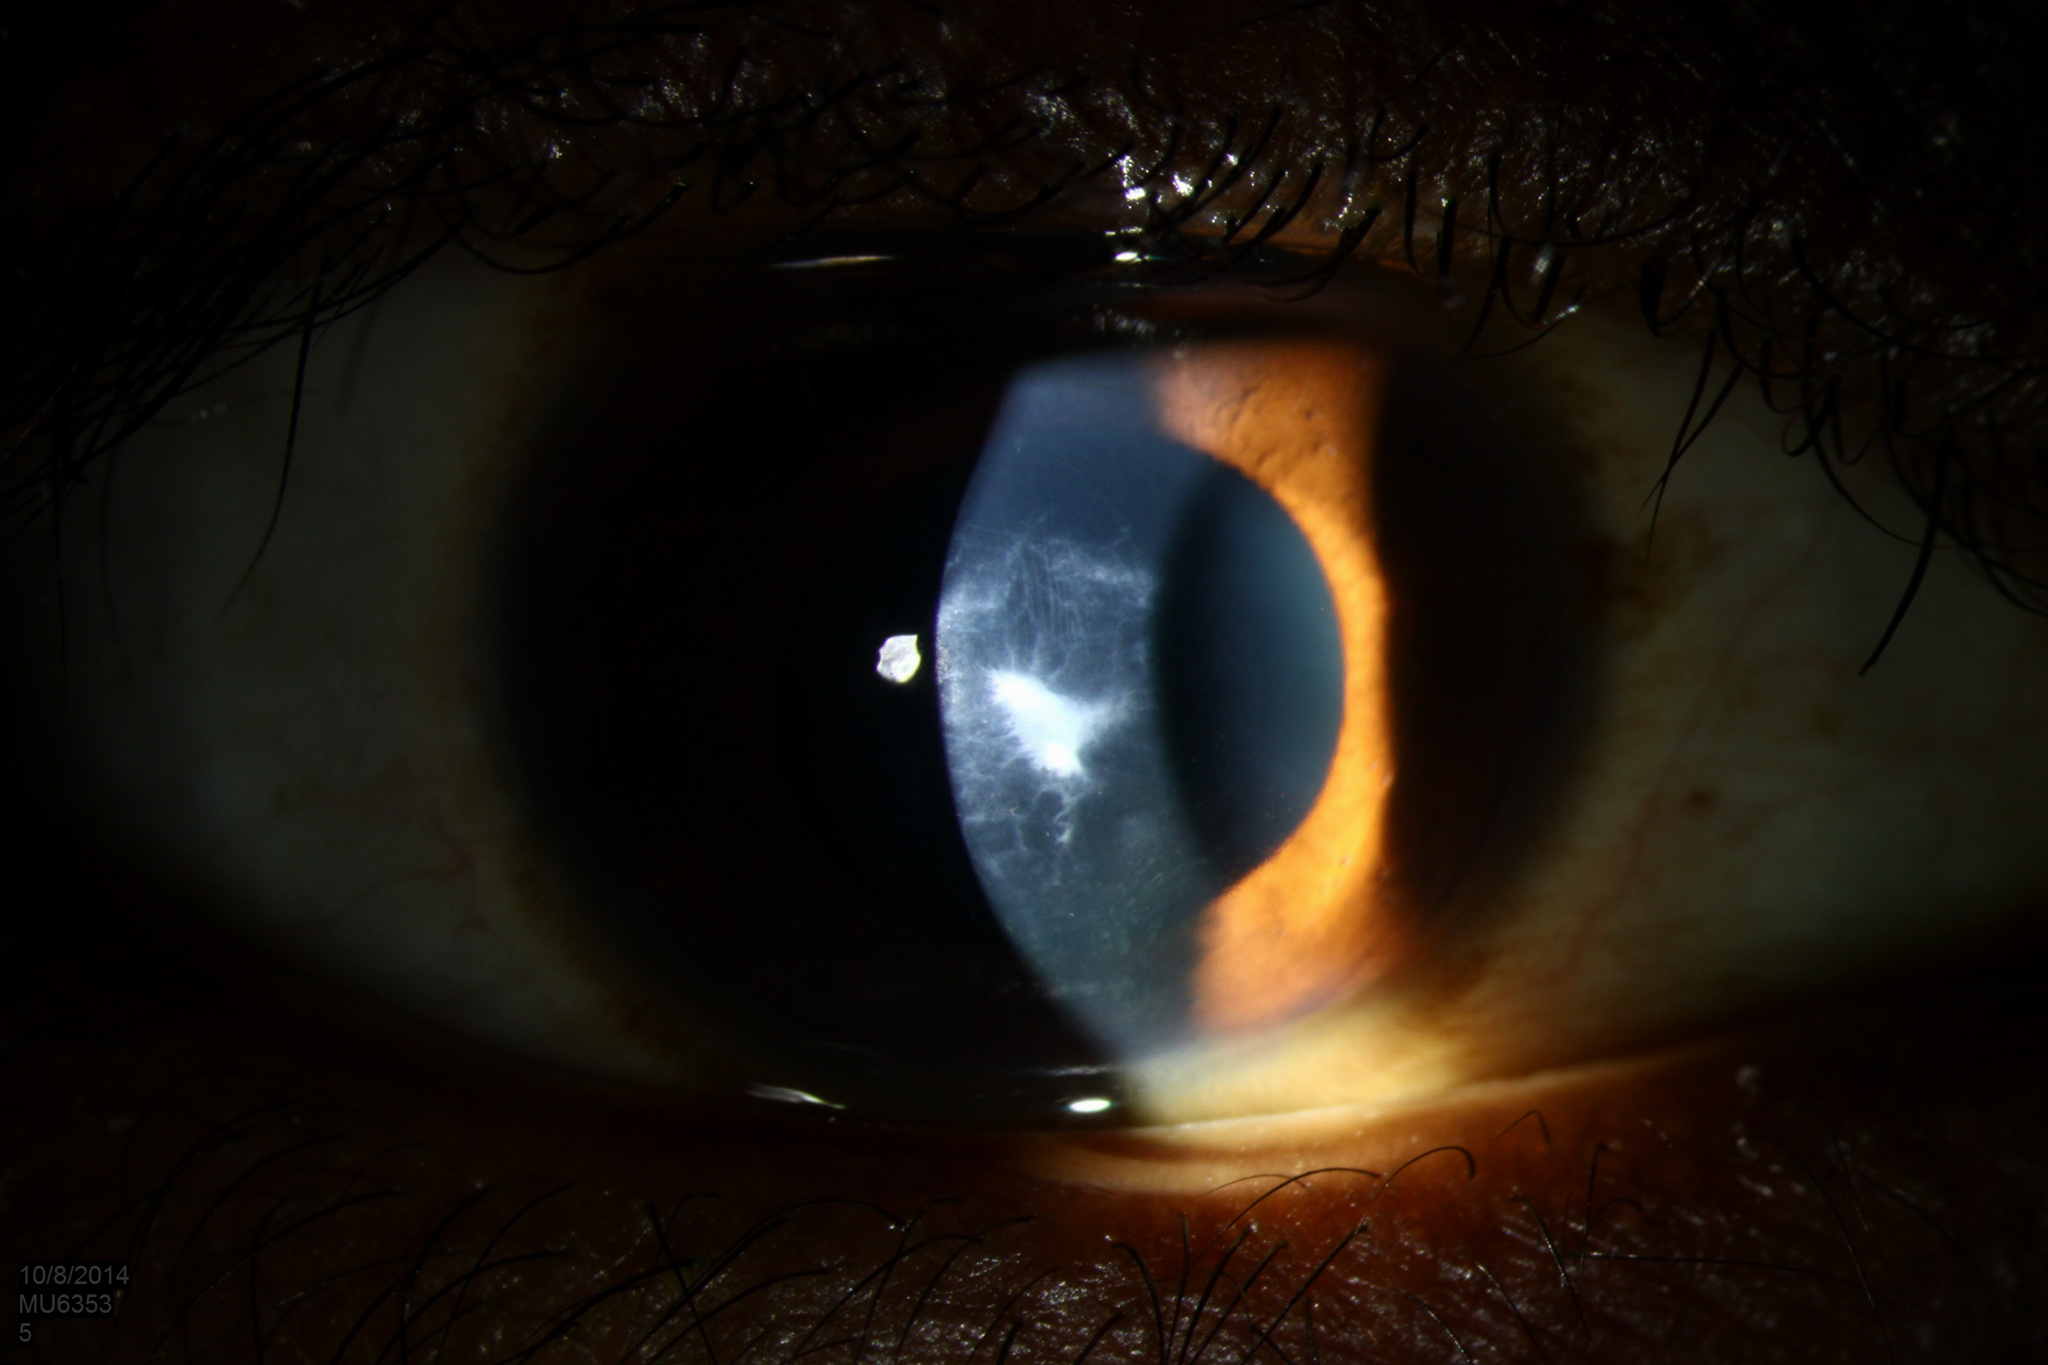

Clinical signs of keratoconus (a) apical scarring with thinning, (b)... Download Scientific What Causes Apical Scarring pulmonary fibrosis, or lung scarring, causes thickened and less elastic lung tissue. In this case, the normally thin, lacy walls of the air sacs in. It’s normal for the lungs to become damaged from environmental toxins, medications, lung. pulmonary fibrosis is a serious, lifelong lung disease. biapical pleural parenchymal scarring is a condition characterized by the presence. What Causes Apical Scarring.

From eyerounds.org